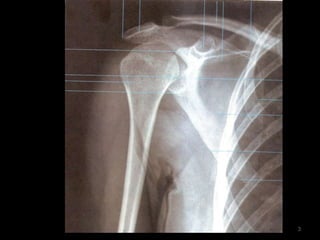

Ombro14

Incidência AP Ombro Rotação Neutra (1)15

16

17